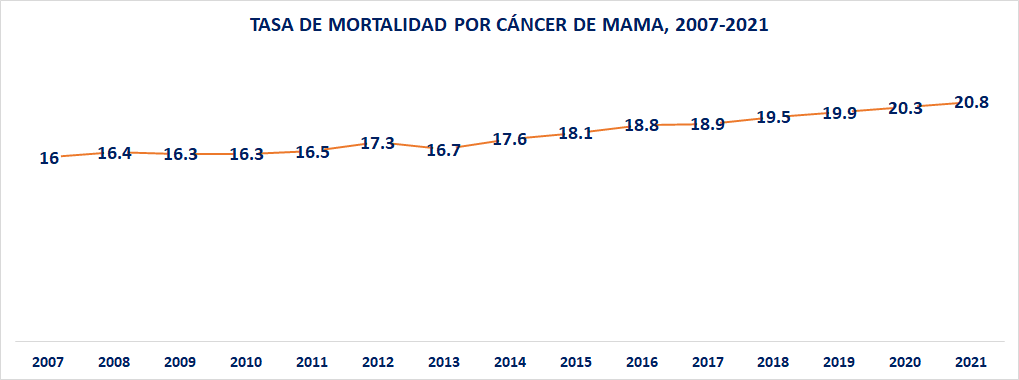

A diferencia del cáncer de cérvix, causa por la cual se ha logrado, hasta ahora una reducción en la tasa de mortalidad; aunque un número casi constante en el número absoluto de decesos anuales; en el caso del cáncer de mama México ha experimentado un muy importante incremento en el número absoluto de casos de defunción, pero también en la tasa anual.

Por su parte, la tasa de mortalidad ha crecido en 23.1% entre el año 2007 y 2021. En efecto, pasó de una tasa de 16 defunciones por cada 100 mil entre 25 y 64 años, a 17.3 en el 2012; a 19.5 en el 2018; y a una estimación de 20.8 en el año 2021.